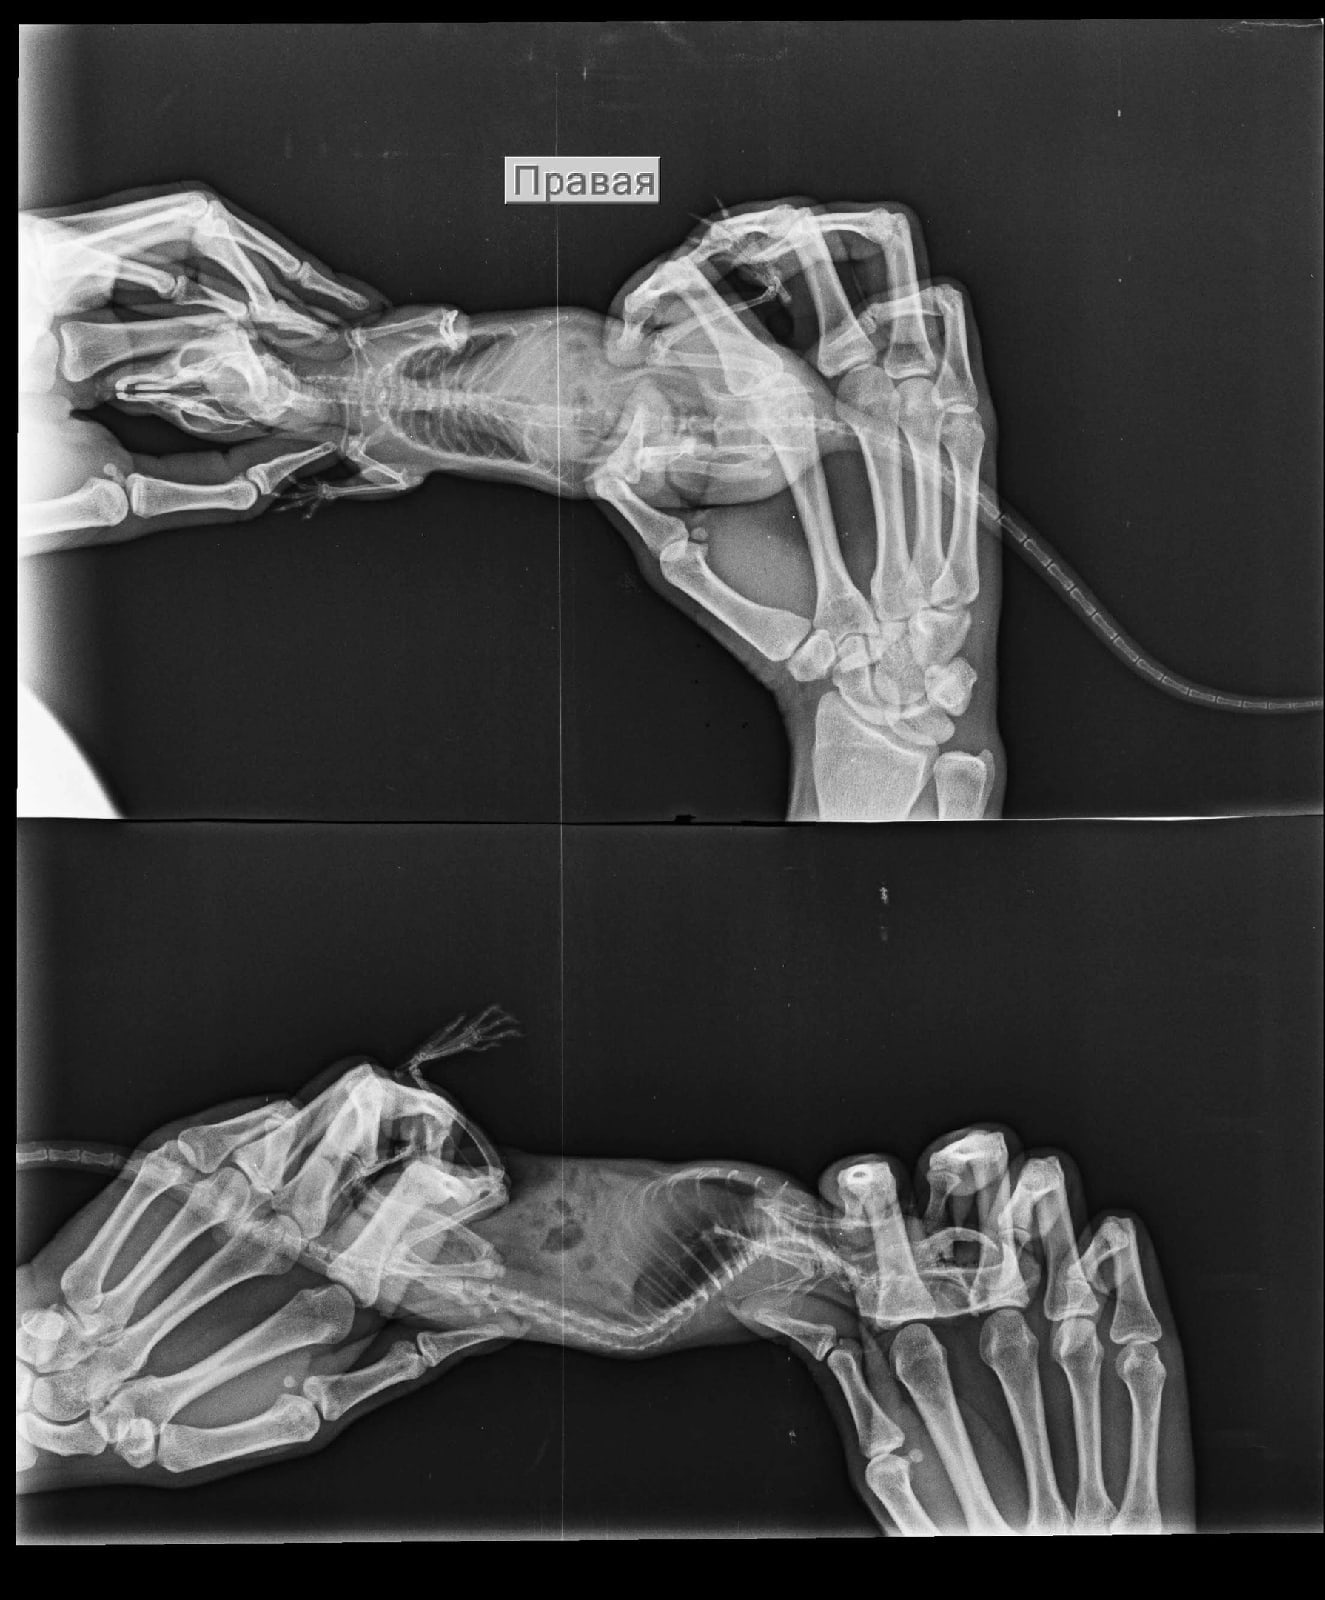

Добрый вечер, дополним историю лечения: лечились небулайзером беродуал 1мл + 4мл физраствор и ципрофлоксацин 50/50 с физраствором. Довольно долгое время. Ещё прикрепляем старые рентгены.

Вложения

r79B2LOR8LM.jpg

EAhluMIaX38.jpg

EAhluMIaX38.jpg (172.14 КБ) 32949 просмотров